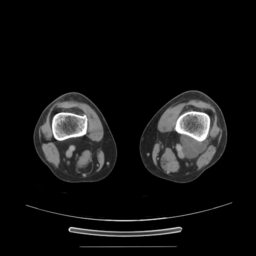

![]() |

| (a) | (b) | (c) | (d) |

Unsupervised Categorization: Our category discovery clusters are generally visually coherent within the cluster and size-balanced across clusters. However, image clusters formed only based on text information (of radiology reports) are highly unbalanced [49], with three clusters inhabiting the majority of images. Note that our method imposes no explicit constraint on the number of instances per cluster. Fig. 6 shows sample images and their top-10 associated key words from two randomly selected clusters (more results are provided in the supplementary material). The LDPO clusters are found to be clinically or semantically related to the corresponding key words, which describe presented anatomies, pathologies (e.g., adenopathy, mass), their associated attributes (e.g., bulky, frontal) and imaging protocols or properties.

The category discovery clusters employing our LDPO method are found to be more visually coherent and cluster-wise balanced in comparison to the results in [49] where clusters are formed only from text information ( radiology reports). Fig. 7 Left shows the image numbers for each cluster from the AlexNet-FC7-Topic setting. The numbers are uniformly distributed with a mean of 778 and standard deviation of 52. Fig. 7 Right illustrates the relation of clustering results derived from image cues or text reports [49]. Note that there is no instance-balance-per-cluster constraints in the LDPO clustering. The clusters in [49] are highly uneven: 3 clusters inhabit the majority of images. Fig. 6 shows sample images and top-10 associated key words from 5 randomly selected clusters (more results in the supplementary material). The LDPO clusters are found to be semantically or clinically related to the corresponding key words, containing the information of (likely appeared) anatomies, pathologies (e.g., adenopathy, mass), their attributes (e.g., bulky, frontal) and imaging protocols or properties.